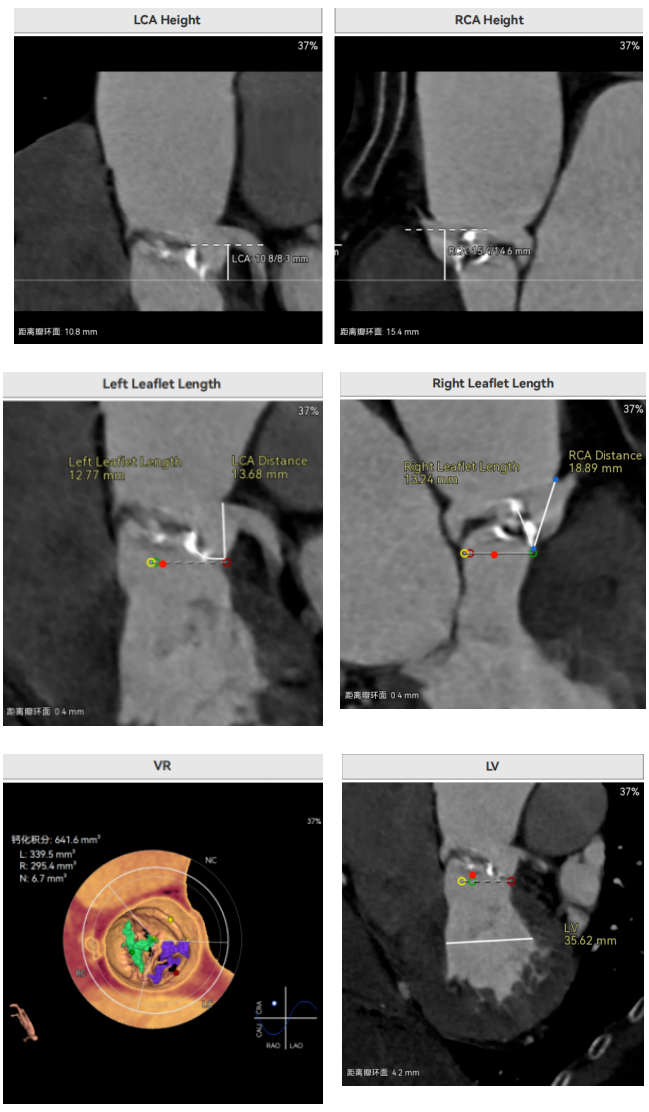

许金鹏教授 安徽省胸科医院 干瓣耐久首选之,15年承诺佑病患:随着病患的复杂性提高及TAVR二次手术窗口期的慢慢到来,摆在临床面前的是如何提升瓣膜使用的耐久性?预装干瓣的获批上市无疑为临床提供了全新的选择。预装干瓣摆脱了传统戊二醛保存的束缚,通过专利抗钙化技术及干式保存工艺打造了一款兼具“曲柔性”和“不沾钙”瓣叶的介入瓣,预期会有更耐久的使用寿命。此次病例患者小瓣环,Prostyle A®自膨瓣的收腰设计,为冠脉开口预留了“生命通道”,而平衡的收腰设计又很好的保证了开口面积,为小瓣环患者血流动力学提供的牢靠的保障。 期待这样一款基于临床需求的性能平衡的耐久干瓣,护佑 TAVR广大患者的全生命周期管理! 患者病史 主要诊断:非风湿性主动脉瓣狭窄(重度);非风湿性主动脉瓣关闭不全(中度);非风湿性二尖瓣关闭不全(中度);心脏扩大(左房明显扩大、左室略大);肺动脉高压(估测肺动脉收缩压约 39mmHg);胸椎压缩性骨折(T9 椎体,考虑新鲜);肺部阴影(两肺慢支改变、多发结节);胆囊术后; 入院检查:BP 109/60mmHg、心率 77 次 / 分(律齐),神清精神可,口唇不绀。 术前超声提示 主动脉瓣钙化并狭窄(重度)伴反流(中量),Vmax509cm/s,PGmax105mmHg;升主动脉增宽;左房明显增大,左室略大;二尖瓣关闭不全伴反流(中+量);瓣尖轻微增厚;室间隔增厚; 术前CT 三叶瓣(L-N融合,功能型二叶瓣),瓣叶增厚中度钙化,钙化主要分布在左冠窦瓣叶边缘及左无融合处、右冠瓣叶基底及边缘,主动脉瓣环径22.2mm,LVOT21.1mm,呈略直通型;双侧冠脉开口高度可,窦部空间大,VTC距离够,预估冠脉低风险,STJ、升主动脉内径可;左室内径可,主动脉水平夹角47°,非横位心。主动脉弓角弓距可;外周入路无明显迂曲,无钙化,两侧股动脉内径可,均可通过20F大鞘,右股低分叉。 手术策略 推荐右侧股动脉为主入路,左侧股动脉为辅助入路,使用20F大鞘,右股分叉上方1cm穿刺。推荐选择AV23瓣膜,18mm球囊预扩,最终理想位置瓣下2mm。 手术过程 在右股动脉穿刺建立通路后,顺利送入大鞘,经食道超声及血管造影确认路径稳定。18mm球囊预扩后评估冠脉灌注良好,后将Prostyle A® AV23瓣膜精准释放于目标位置,超声显示无瓣周漏,术后即刻造影显示无明显反流,导管测平均跨瓣压差8mmHg,心功能明显改善,患者生命体征平稳。 主动脉根部造影 18号球囊预扩 输送器顺利过弓 迅速锚定,平稳释放至工作位 最终造影,位置形态良好,无瓣周漏 Prostyle A®预装干瓣——助力临床最优化解决方案 预装干瓣 便捷顺安:金仕生物专利抗钙化技术运用纳米技术去除组织内的细胞碎片和磷脂,封闭游离醛基,从根本上阻断了瓣膜钙化的多项因素,显著提升了瓣膜的耐久性;同时,相比较传统戊二醛保存方式,干式存储最大限度的保留心包的亲水亲油平衡,还原组织天然曲柔性,进一步保障了瓣叶开合,保证长期耐久性; 流入端桶状设计:流入端桶状的设计,迅速稳定锚定,减少手术时间的同时进一步保障了术中安全; 平衡的收腰设计:该病例左冠高度10.8mm,AV23瓣膜的平衡收腰设计既确保了冠脉开口安全性,又保证了EOA,有效降低了循环崩溃风险,而术后8mmHg的压差的表现更加证明了优秀的血流动力学,进一步提高了瓣膜的耐久性。 专家简介 许金鹏 安徽省胸科医院(点击查看专家详细简历) · END ·